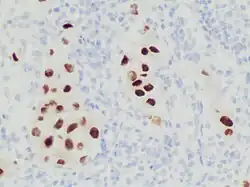

Immunohistochemistry stain for SOX10 in a poorly differentiated metastatic melanoma to a lymph node, helping in its diagnosis.